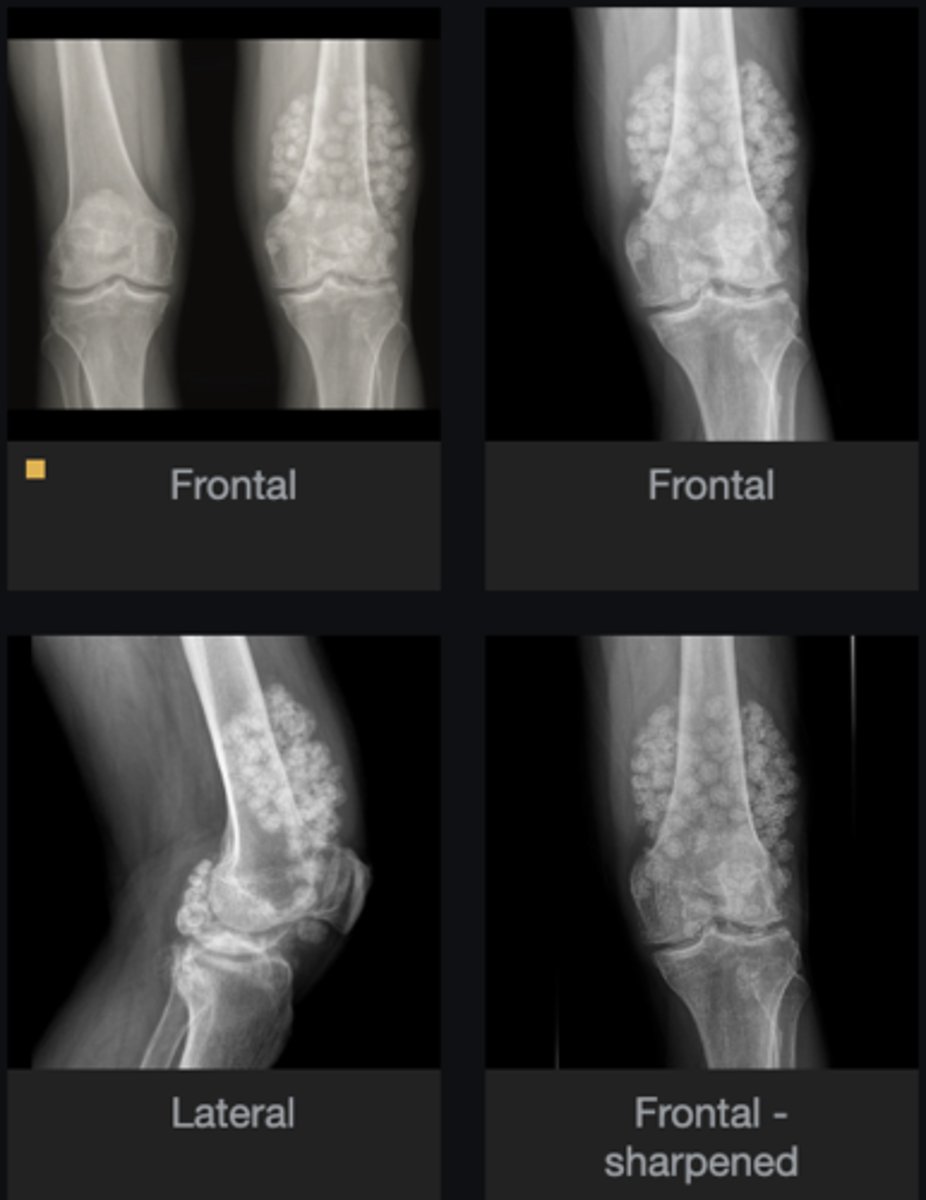

- Subluxation

- Non-uniform loss of joint space (medial tibiofemoral joint)

- Osteophytes

- Subchondral sclerosis

Describe findings

Osteoarthrosis

Diagnosis?

Genu varum

Clinically, the patient's lower extremities would take on what kind of appearance?